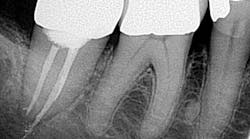

• Missed canals

Know your tooth anatomy and the possible variations of the canals (figure 2). The molars present with the most diverse canal composition—“additional canals in the mesial roots of maxillary molars and the distal roots of mandibular molars are the most frequently missed” (2)—but even the premolars and incisors can prove to be a formidable foe. Remember the article by David Landwehr, DDS, MS, titled “The myth of ‘easy’ root canals in endodontics”? Read it if you haven’t. Lastly, don’t skimp on your occlusal access and use magnification.